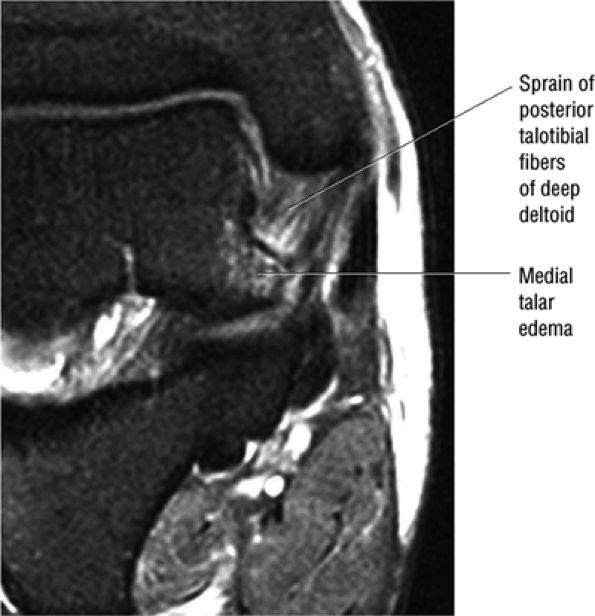

fascicle inserts onto the superior border of the calcaneona vicular ligament. The deep part of the deltoid, which is rectangular, consists of a small anterior component (the anterior tibiotalar ligament) and a strong posterior component (the posterior tibiotalar ligament) (Fig. 5.64). The posterior tibiotalar ligament represents the strongest part of the entire medial ligament complex. The deep portion of the deltoid ligament, covered by synovium, is intra-articular.

![]() |

|

FIGURE 5.58 ● transverse section through the midcalf shows the anterior and lateral compartments and their contents.